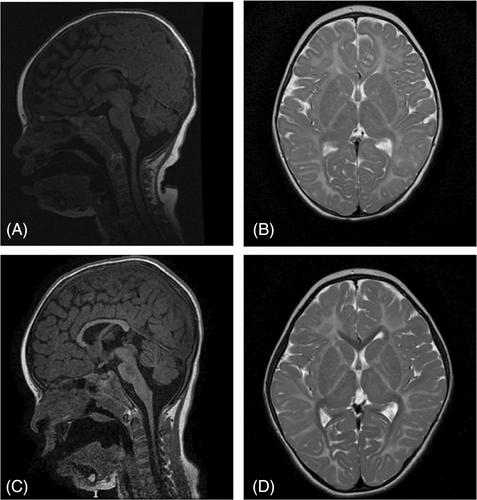

两兄妹表现为神经代谢表型,被鉴定为 5、10-甲苯四氢叶酸合成酶(MTHFS)缺乏症。两名患者的全基因组测序结果显示,他们都患有同基因的 MTHFS 变异 NM_006441.3(MTHFS):c.434G > A, p.Arg145Gin。基线时,两名患者均表现为中度高同型半胱氨酸血症,全血中 5-甲基四氢叶酸(5MTHF)减少,5-甲酰四氢叶酸(5-FTHF)增加。在脑脊液中,5-甲基四氢叶酸水平处于正常值的较低水平,而 5-FTHF则显著升高。在我们的新型酶测定中,两姐妹培养的成纤维细胞中都缺乏 MTHFS 活性。我们开始口服治疗,5-甲基四氢叶酸(5MTHF)的剂量每天递增到 12 毫克,羟钴胺每天 5 毫克。两名患者的血浆同型半胱氨酸均恢复正常,而血液中的 5MTHF 出现升高。治疗后,血液和脑脊液中升高的 5FTHF 水平进一步升高。这一治疗方案使患者 1 的临床症状有所改善。在患者 2 中,补充 5MTHF 的临床疗效并不明显。看来,缓解 5MTHF 水平的不足和使血液中的同型半胱氨酸恢复正常会带来一些临床益处。另一方面,高水平的 5FTHF 很可能是有害的,并可能促使我们减少 5MTHF 的剂量。此外,我们还假设,瘫痪的 MTHFS 酶可能会破坏嘌呤酶体的稳定性,而 5MTHF 可能无法改善这种情况。

Two siblings, presenting with a neurometabolic phenotype, were identified with 5, 10-methenyltetrahydrofolate synthetase (MTHFS) deficiency. Whole genome sequencing in both patients demonstrated an homozygous MTHFS variant NM_006441.3(MTHFS):c.434G > A, p.Arg145Gin, which has been described before. At baseline, both patients showed moderate hyperhomocysteinemia, decreased 5-methyltetrahydrofolate (5MTHF), and increased 5-formyltetrahydrofolate (5-FTHF) in whole blood. In CSF, 5MTHF levels were in the low-normal range and 5-FTHF was strongly increased. In our novel enzyme assay, MTHFS activity was deficient in cultured fibroblasts in both sisters. Oral treatment was initiated with escalating dose of 5-methyltetrahydrofolate (5MTHF) up to 12 mg and hydroxycobalamin 5 mg daily. Plasma homocysteine normalized and 5MTHF became elevated in the blood of both patients. The elevated 5FTHF levels increased further on treatment in blood and CSF. This regimen resulted in some clinical improvement of patient 1. In patient 2, the clinical benefits of 5MTHF supplementation were less obvious. It seems plausible that the alleviation of the deficient 5MTHF levels and normalization of homocysteine in blood are of some clinical benefit. On the other hand, the very high levels of 5FTHF may well be detrimental and may prompt us to decrease the dose of 5MTHF. In addition, we hypothesize that the crippled MTHFS enzyme may destabilize the purinosome, which is presumably not ameliorated by 5MTHF.